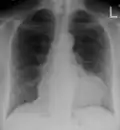

-

A pericardial effusion as seen on CXR in someone with pericarditis

The diagnosis of tamponade can be confirmed with trans-thoracic echocardiography (TTE), which should show a large pericardial effusion and diastolic collapse of the right ventricle and right atrium. Chest X-ray usually shows an enlarged cardiac silhouette ("water bottle" appearance) and clear lungs. Pulmonary congestion is typically not seen because equalization of diastolic pressures constrains the pulmonary capillary wedge pressure to the intra-pericardial pressure (and all other diastolic pressures).